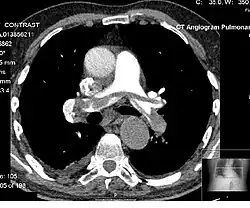

Computed tomography angiography (CTA) is a type of contrast CT to visualize the arteries and veins throughout the body.[111] This ranges from arteries serving the brain to those bringing blood to the lungs, kidneys, arms and legs. An example of this type of exam is CT pulmonary angiogram (CTPA) used to diagnose pulmonary embolism (PE). It employs computed tomography and an iodine-based contrast agent to obtain an image of the pulmonary arteries.[112][113]